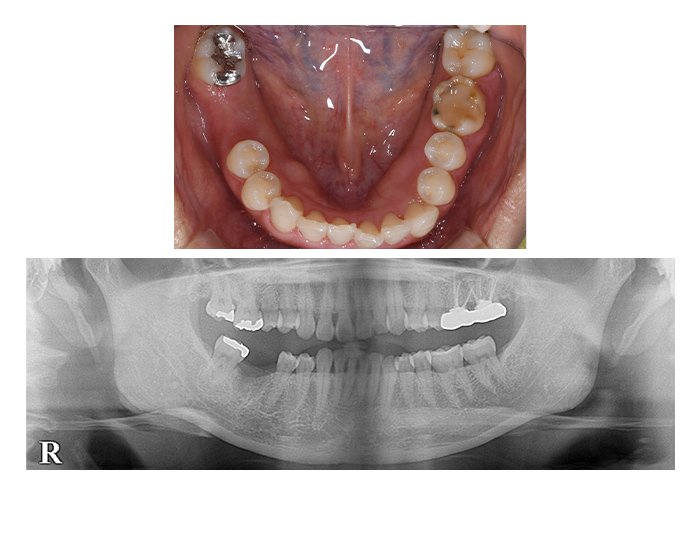

症例01 奥歯のインプラント

(女性、期間4カ月)

BEFORE(術前)

AFTER(術後)